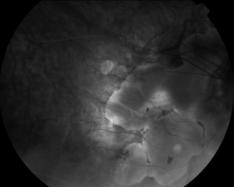

IM000038.JPG